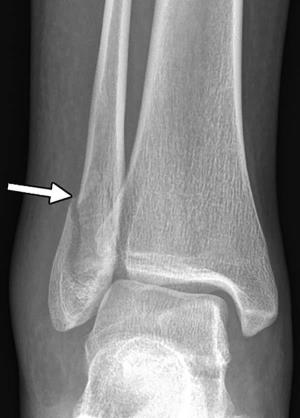

X-ray of the right ankle in a 24-year-old woman who presented with pain after a fall and was found to have a lateral malleolar fracture (arrow). She later stated that her boyfriend pushed her after an argument, causing her to fall and twist her ankle.